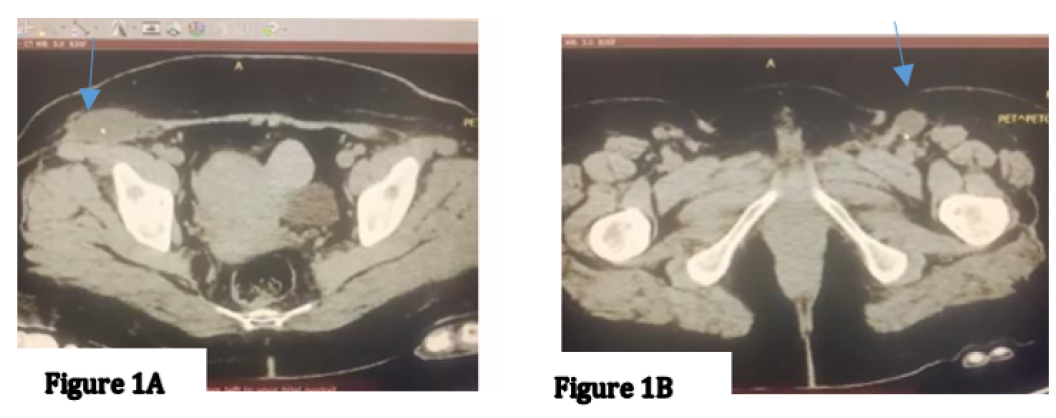

Challenges in Diagnosis and Surgical Management of Locally Advanced Vulvar Melanoma

Eliona Demaliaj, Daniela Nakuci, Erisa Kola, Arben Gjata and Fatjon Balla. 12(4): 18-23.